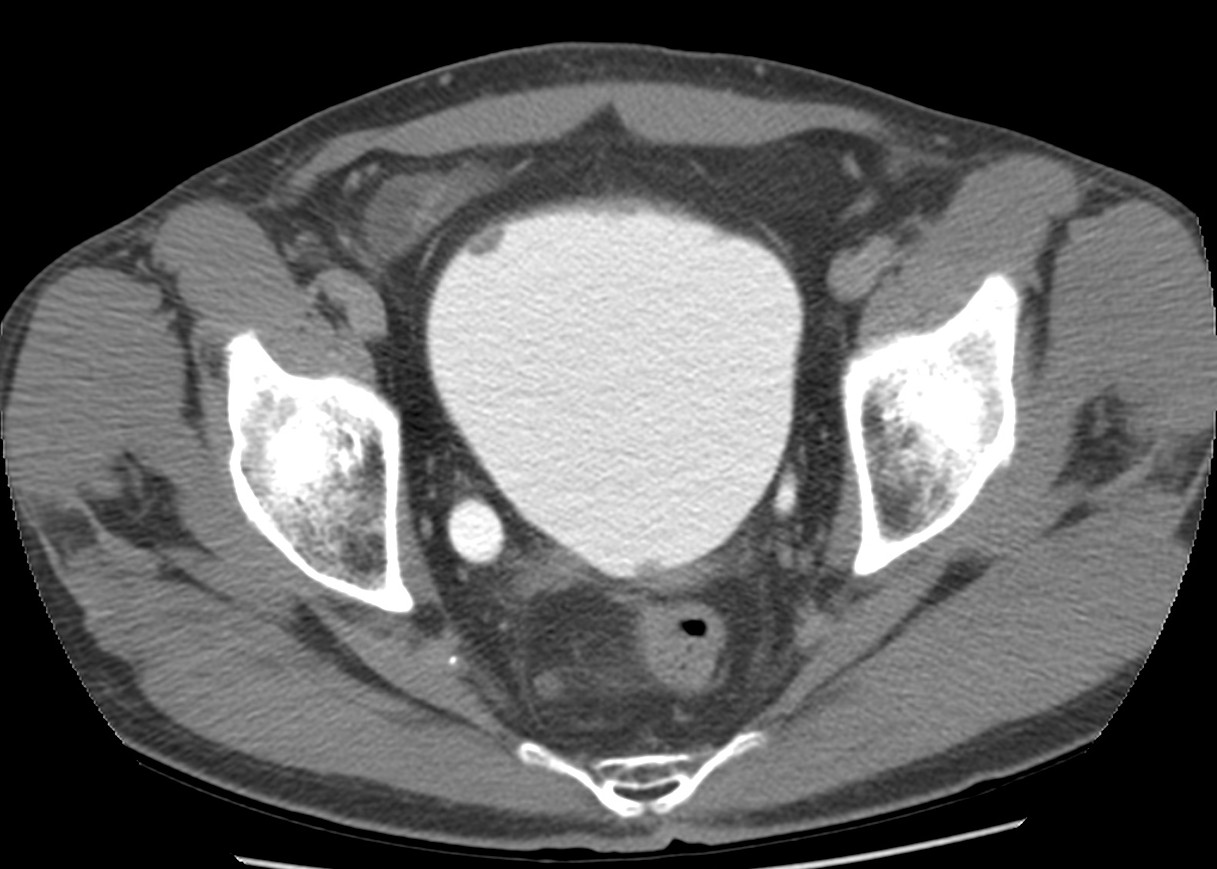

CASO CLÍNICO: Recopilatoción.

Paciente de 59 años con antecedentes personales de Cá de vejiga.

Se le realiza una Uro-Tc por seguimiento al año, aunque en esta ocasión el paciente refiere episodio de hematuria.

Tras el tratamiento de la recidiva y nefrostomía para la hidroureteronefrosis, vuelve acudir al hospital a los 9 meses por episodio de dolor en FD y malestar general. Se realiza una ecografía de urgencias.

Se realiza nueva TC bifásico abdominopélvio y Uro TC.

- Paciente con numerosas recidivas por Cá vejiga.

- Ha desarrollado un tumor metacrónico en pelvis renal derecha, también responsable de la hidroureteronefrosis.

- Mala evolución radiológica del proceso a expensas de metástasis pulmonares y hepáticas.